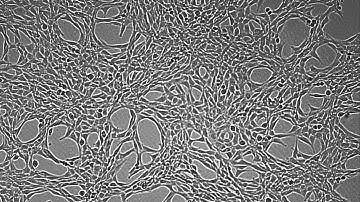

00b 070625 hepG2 CCCP TMRE 3 R3D